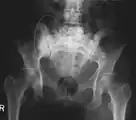

3D rendered CT scan of bone metastases of the hip bone, in a 60 year old woman with parotid gland cancer. Large lesions are seen on the hip on the more distant side. Involvement of the spine has caused a compression fracture.